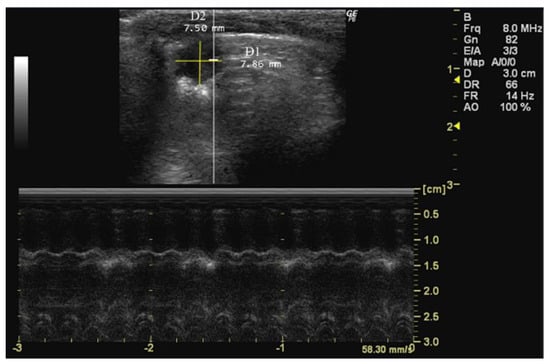

- How to measure D1 and D2